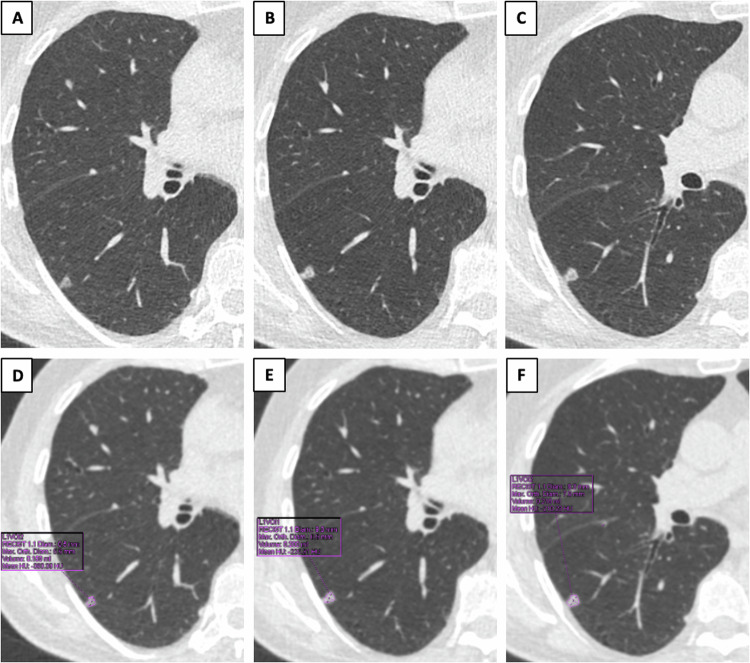

Any screening is supposed to carry the risk of overdiagnosis and overtreatment, whereby cancers that would have not affected life expectancy because of their less aggressive behavior and/or participant’s comorbidities undergo invasive treatment [21]. It has been shown that less aggressive LCs more commonly manifest as subsolid nodules (Fig. 1), reflecting a preinvasive or minimally invasive histology [22–24]. Although subsolid nodules have a higher likelihood of malignancy as compared to solid nodules, they tend to have indolent clinical behavior and long-term survival without intervention [25]. The progression toward more invasive forms is demonstrated by the development of a solid component or by an increase in the size of a pre-existing solid component. As observed by Silva et al [26], these morphological changes, typically occurring at a slow rate, can be safely detected on serial LDCT performed within an LCS setting. Based on current evidence, long-term LCS may offer an opportunity for a more conservative approach to screening detected subsolid nodules.

Fig. 1.

Example of a lung adenocarcinoma presenting as a non-solid nodule at baseline LCS low dose computed tomography (A), which developed a solid component at 12-months follow-up (B). A further increase in nodule size and density is shown in C. Nodule size and density for the three-time points are shown in D–F, respectively